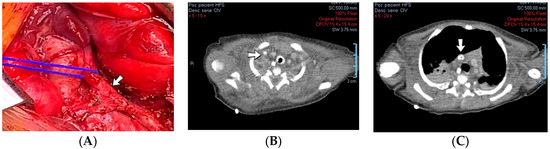

4.39. Case No. 39—Postnatal Thrombosis of Both Internal Jugular Veins, Both Brachiocephalic Veins, the Superior Vena Cava, the Inferior Vena Cava, Both Common Iliac Veins, Both External Iliac Veins, and Both Femoral Veins

A 6-week-old male neonate (29 weeks, 1.23 kg), the first twin from a twin pregnancy, known with cardiopulmonary arrest with prolonged cardiopulmonary resuscitation, presented with severe bronchopulmonary dysplasia. The admission laboratory findings showed leukocytosis, modified coagulation tests, elevated D-dimer tests, and sepsis with Pseudomonas aeruginosa. During hospitalization, the patient suffered multiple fractures of the humerus, femur, tibia, and costal ribs.

A cardiovascular ultrasound revealed thrombosis of the right internal jugular and brachiocephalic veins. Therefore, the central venous catheter from the right internal jugular vein was removed, and two other central lines were inserted on the right femoral vein and on the left internal jugular vein. Despite initiating anticoagulant treatment with heparin, followed by bivalirudin and fibrinolytic agents like alteplase, the CT angiography indicated an extension of the thrombus to the right atrium (Figure 18). A thrombectomy and pericardial patch venoplasty were performed at four months of age. Despite the double anticoagulation treatment with heparin and bivalirudin, the superior vena cava syndrome clinically persisted, and thrombosis of the left internal jugular and brachiocephalic veins also occurred. Thrombosis of the inferior vena cava, both common iliac veins, external iliac veins, and femoral veins were diagnosed in turn. The patient died at 14 months of life due to cardiopulmonary arrest.

Figure 18.

Case no. 39. During surgery, a fibrous band (A) was noticed between the right internal jugular and brachiocephalic veins. Thrombosis of the right internal jugular vein (B) and the superior vena cava (C) was identified on Angio-CT.

A suspicion of inherited thrombophilia was raised, and genetic testing confirmed it, with a positive MTHFR C677T homozygous gene mutation and antithrombin deficiency. Normal PAI-1 levels were detected. There was a positive family history of thrombosis—the second twin from the delivery, who died at six weeks of life, presented cerebral venous sinus thrombosis on the brain ultrasound from admission.